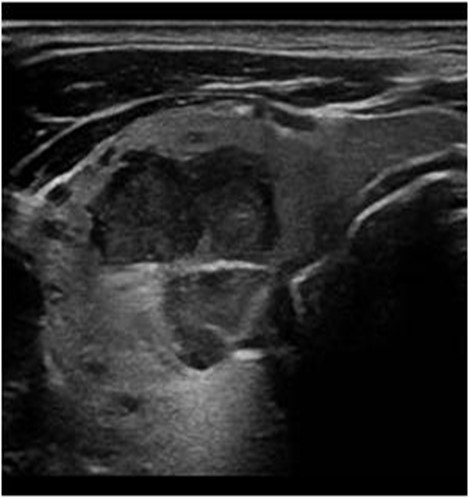

Thyroid nodules are common and often discovered incidentally during routine check-ups.

- Advanced thyroid ultrasound imaging

- Ultrasound-guided fine needle aspiration biopsy